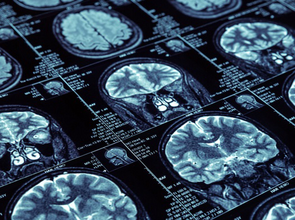

Hier finden Sie aktuelle Nachrichten und Fakten aus der Arbeit der Schlaganfall-Hilfe.